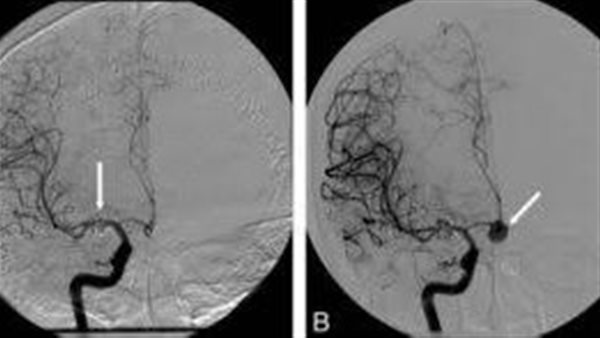

وتبين للأطباء من خلال فحص الرنين على شرايين المخ، أن هذا النزيف بسبب وجود تمدد بشرايين بالمخ الذي تسبب في حدوث ضعف في الجانب الأيمن الذي ظهر خلال يومين من المتابعة، والذي استوجب إجراء قسطرة مخية لغلق التمدد شرياني على الفور بأحد الطرق التداخلية الأنسب للإغلاق، "Simple coiling،Stent assissted coiling Flow divertor".

كما تمكن الأطباء من تشخيص حالة مريض 40 عامًا، يعاني من نوبة تشنجات وبعد المتابعة الكثيفة والأشعة المقطعية على المخ، تبين وجود نزيف تحت الأم العنكبوتية ومن الرنين على شرايين وأوردة المخ، وتبين أن هذا النزيف بسبب وجود تشوه شرياني وريدي بالمخ، الذي كان سببًا في حدوث نزيف متكرر على مدار السنين الماضية، والذي سيظل يتكرر إذا لم يتم علاج التشوه، وقد تقرر إجراء قسطرة مخية لغلق التشوه الشرياني الوريدي بواسطة الحقن Onyx بمادة ومادة Histoacryl /lipidol .